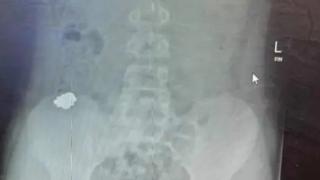

Това е само един от зачестилите през последните месеци случаи у нас на поглъщане на магнитни топчета

За да се сдобие със суперсили, 12-годишното момче погълнало 54 магнитни топчета

Момчето е успяло да избегне сериозни наранявания и сложна операция

В Украйна, в град Черновци играчка магнит е влязла в червата на дете, причинявайки остро възпаление,...